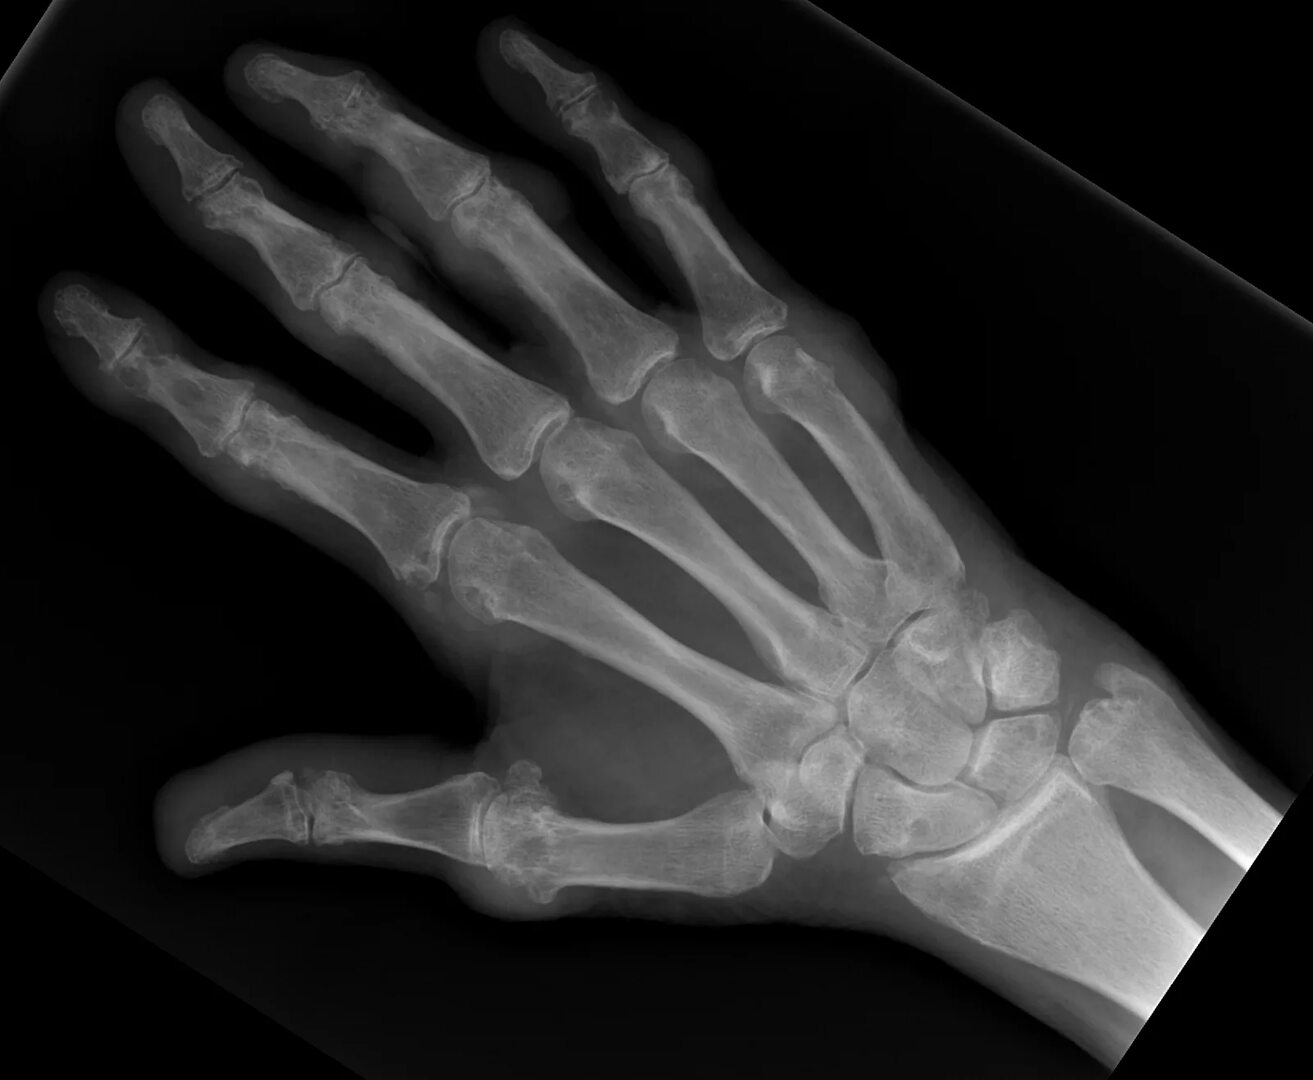

Фотографии рентгенограмм кистей рук в норме